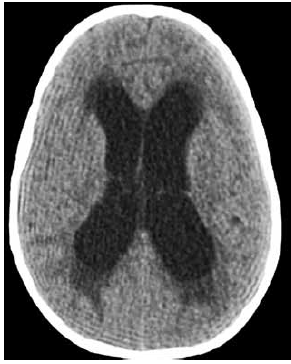

Imagem da tomografia de crânio:

Criança de 2 anos e 8 meses, internada em uma enfermaria, no pós-operatório de uma neurocirurgia, com queixa de sonolência, tem história de tumor de tronco ressecado há 1 semana, sem a realização de derivação ventrículo peritoneal, pois o neurocirurgião achou desnecessário e optou por observar clinicamente a evolução da criança. Nas últimas 6 horas, está mais sonolenta. Foi avaliada pelo médico hospitalista, que solicitou uma tomografia de crânio, e encaminhada pelo técnico de transporte e transferência para UTI após o exame. No exame de entrada na UTI pediátrica: regular estado geral, descorada+, acianótica, anictérica, bradipneica, afebril, letárgica (sem abertura ocular ao chamado ou à dor, gemência aos estímulos dolorosos, resposta motora com retirada inespecífica à dor), FR – 16 irregular Sat – 92% em nebulização com oxigênio 5l/minuto, PA – 155 x 100 mmHg, FC – 65 bpm, pulsos firmes, tempo de enchimento capilar – 2 segundos.